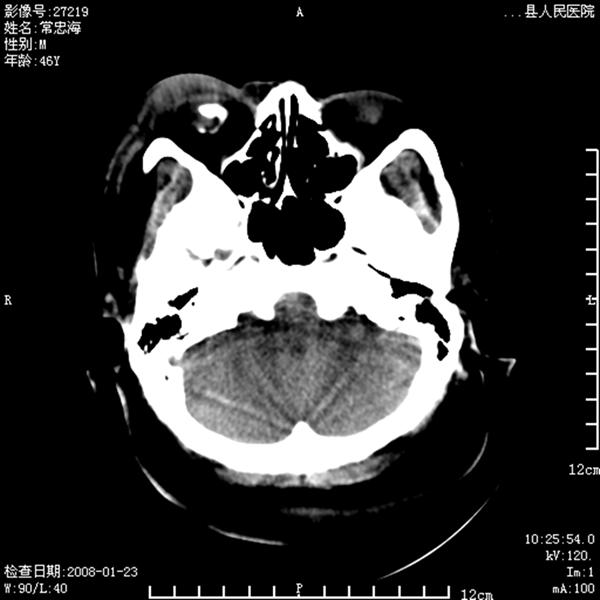

以下是引用江边学者在2008-4-19 22:26:00的发言:[br]1.胼胝体发育不良。[br]2.右侧眼球痨。[br]3.右侧颜面部软组织挫伤。